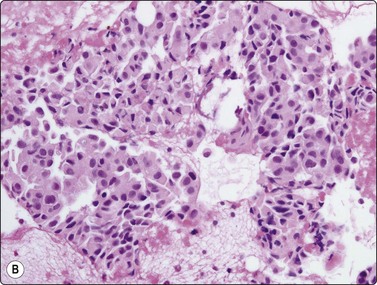

image image

Fig. 8.13 Anthraco-silicosis; progressive massive fibrosis

Bilateral upper zone/hilar lung masses in a miner. Dense masses of macrophages and fibrous tissue (A, H&E, MP; B, H&E, HP).